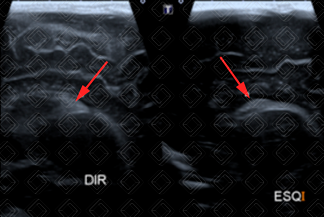

Texto alternativo para a imagem Figura 1. Créditos: Dra. Elazir Mota - Rio de Janeiro/RJ

Descrição das figuras 1 e 2: Ultrassonografia transfontanela; imagens coronal e parassagitais direita e esquerda evidenciando áreas triangulares hiperecogênicas (setas vermelhas) na topografia dos sulcos caudotalâmicos bilateralmente, compatível com hemorragia de matriz germinativa grau I bilateral.

A hemorragia de matriz germinal mais comumente inicia-se no sulco caudotalâmico, podendo estender-se para o interior dos ventrículos laterais, até mesmo para o parênquima cerebral.

• Grau I: Hemorragia presente somente no sulco caudotalâmico (figuras 1 e 2);